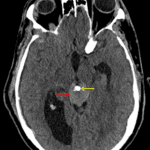

CT

- Mildly hyperattenuating pineal region mass with internal calcification

- Associated obstructive hydrocephalus at the level of the cerebral aqueduct

- Right frontal approach external ventricular drain terminating in the third ventricle